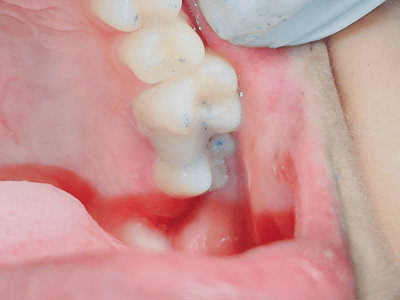

provides expert treatment for gum diseases, receding gums, and dental implant procedures using the

the best possible care for every patient. Whether you need routine checkups or complex periodontal

From routine checkups to complex gum treatments, dental implants, laser dentistry, root canal treatments (RCT), and smile